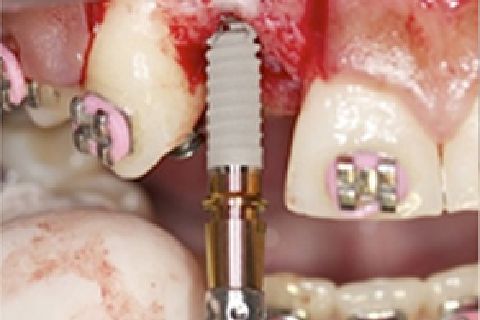

''Neste caso, a paciente gostaria de melhorar a estética do seu sorriso, prejudicada pela agenesia de ambos os incisivos laterais superiores. Devido à baixa disponibilidade óssea, observada na tomografia computadorizada, optou-se pela instalação de implantes estreitos (Xive – Dentsply Implants – 3.0 mm de diâmetro) com regeneração simultânea (Biooss e Biogide – Geistlich), ao invés de realizar enxerto ósseo prévio. Após osseointegração, foi realizado condicionamento gengival com provisórios e novo enceramento diagnóstico. O caso foi finalizado com coroas livres de metal sobre os implantes e microlaminados cerâmicos sobre os incisivos centrais (e.max - dissilicato de lítio – Ivoclar Vivadent), visando o mínimo desgaste de estrutura dental sadia. ''